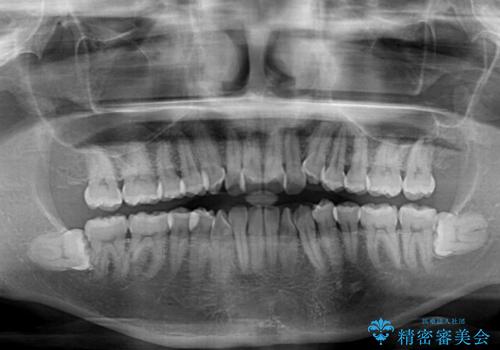

前歯のクロスバイト インビザラインによる矯正治療

- 上下のクロスバイトと前歯のデコボコを気にして来院された患者様です。

インビザラインを用い、IPR(歯と歯の間を削る)と歯列全体を拡大させることで、歯並びを整えていくこととしました。